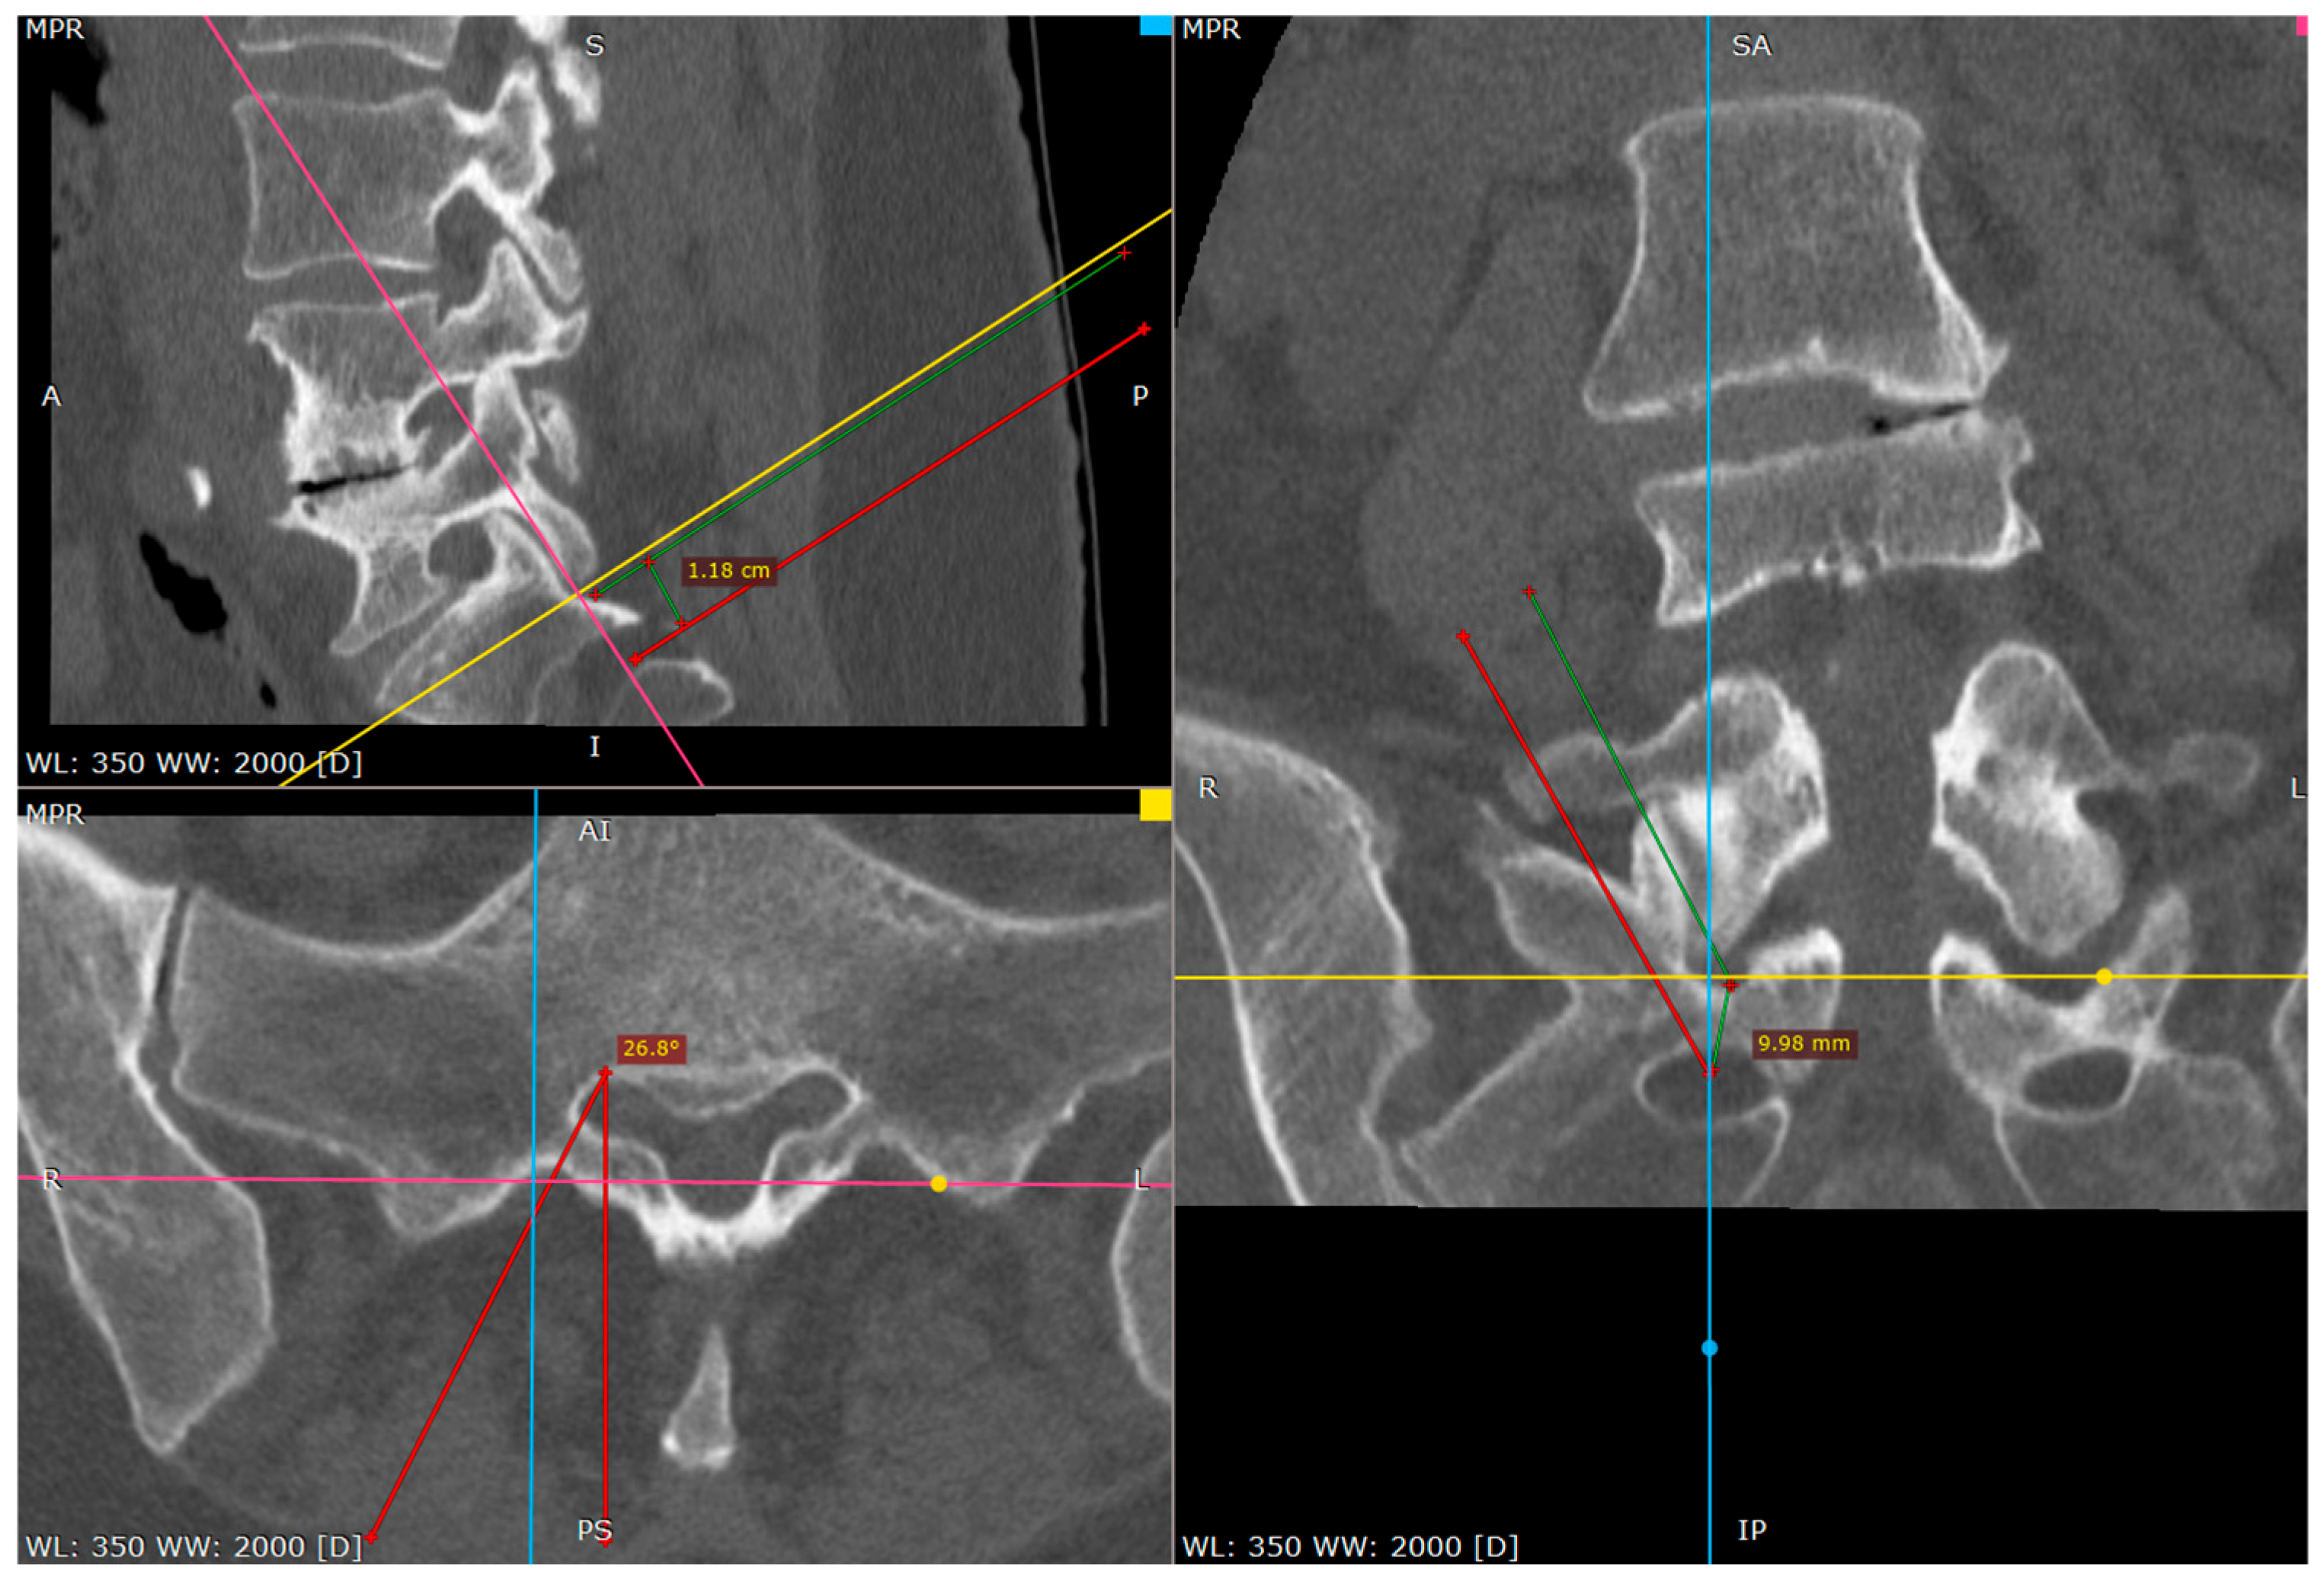

At this phase we start to wander to the caudal direction with the tip of the needle by tapping, moving the tip with a gentle reversing–advancing movement, as well as the twisting of the bended tip (Figure 6).

In a short distance the needle loses the bony contact as it reaches the dorsal foramen of the S1/S2 segment.

It is beneficial to remember the level of it. If we do not perform it by then, the needle can be reversed and placed on the brink of the opening, to give an idea of what the depth is at the start of the opening.

From this point we can gently advance the needle 2–3 cm before we confirm the depth of the needle on the lateral view.

The proper placement of the tip can be confirmed with the contrast administration, fluoroscopy verification or clinical response with the S1 root distribution sensation after the tip of the needle contacts the S1 sheath. Therefore, at this part one should be cautious. We usually use the 1% lidocaine solution to produce the hydrostatic pressure cushion at the tip of the needle, while advancing the needle, as well as a larger needle that poses less risk of penetrating the root sheath. Also, the tapping activity over the bone blunts the tip of the needle, decreasing the risk of root injury (Figure 7, Figure 8 and Figure 9).

Figure 7. Distance between inferior facet surface and dorsal foramina (CT tri-plane reconstruction).

Figure 8. Approach angle and needle trajectory to facet with intent to approach S1 root (CT tri-plane reconstruction).